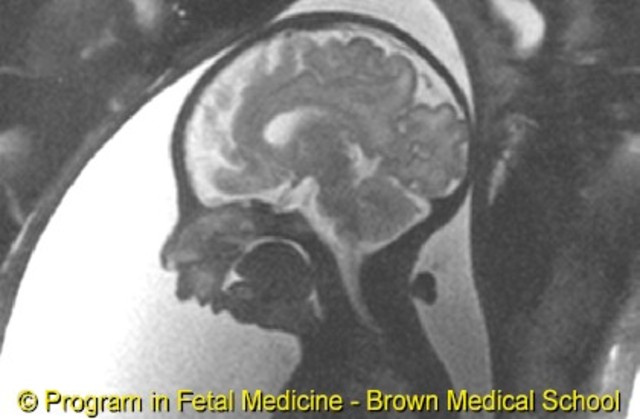

Treacher-Collins (TCS) or Mandibulofacial dysostosis

Affects the development of bones and other tissues in the face. Symptoms of TCS are slanted eyes a malformed lower jaw and ears and other facial deformities